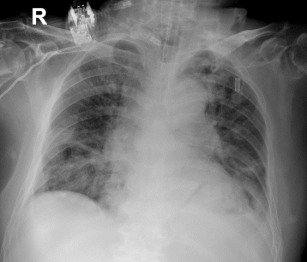

10-25胸部X线

10-28患者病情好转,予以气管拔管